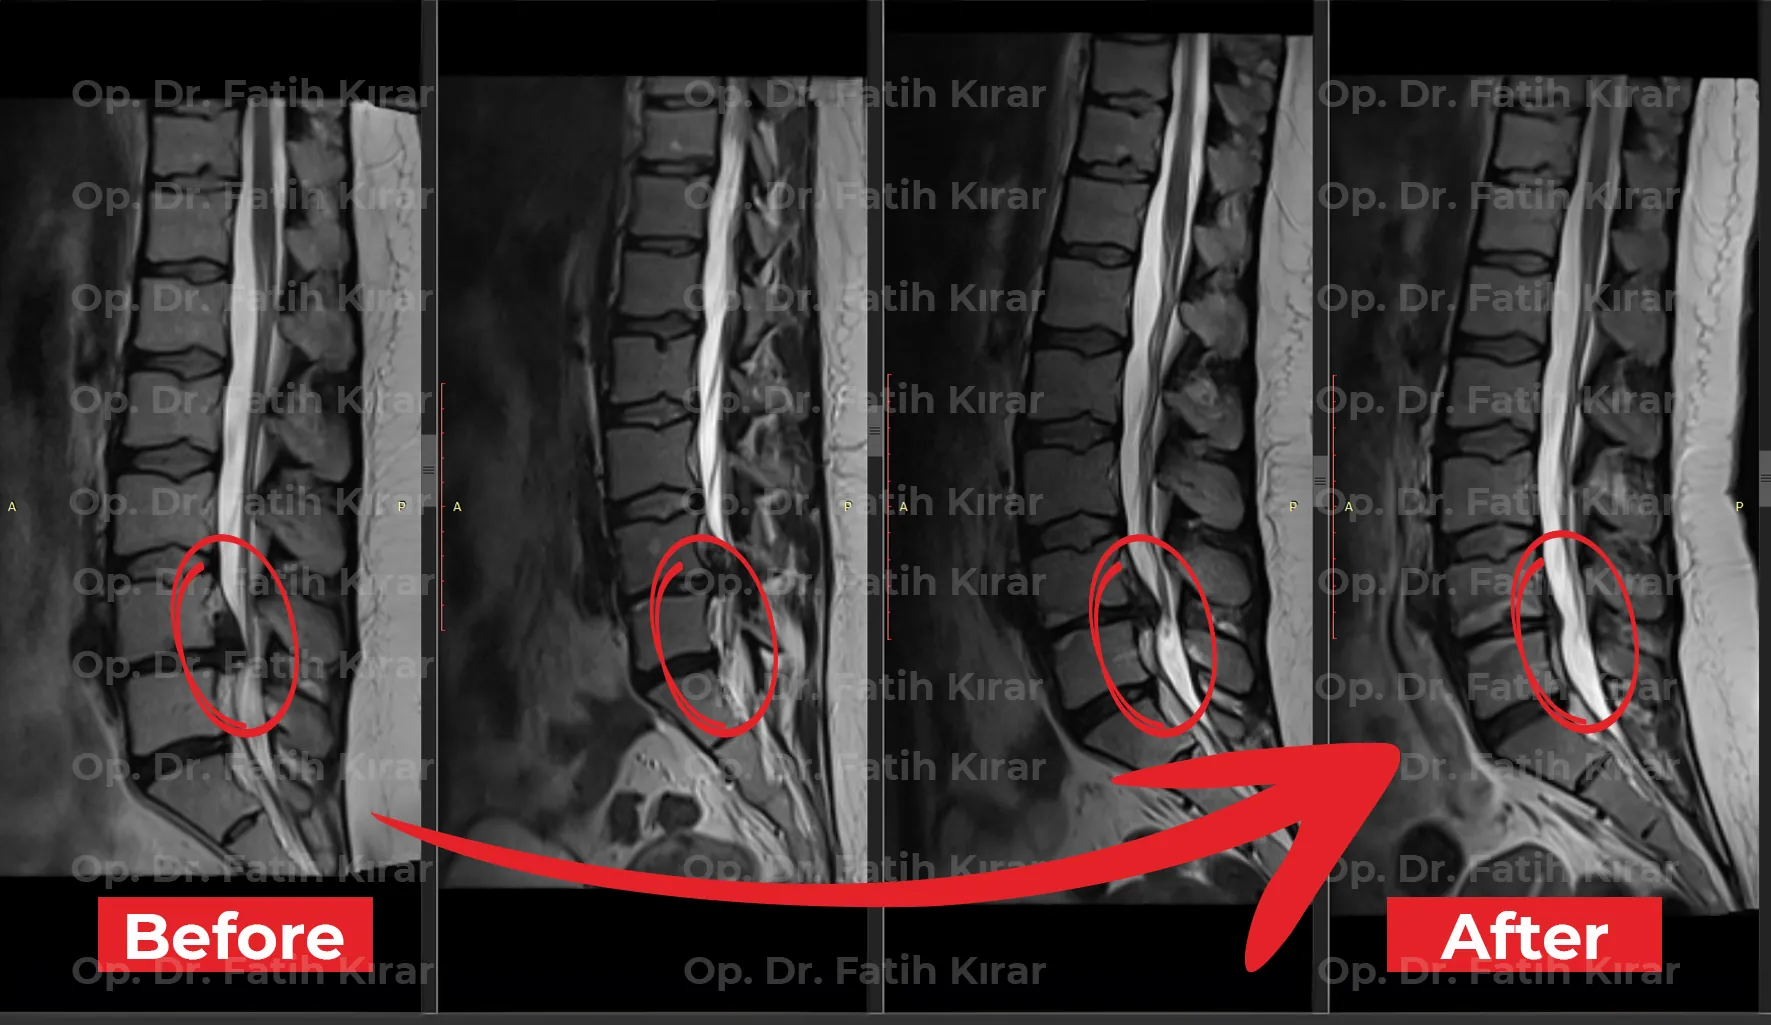

Clinical Results

MRI Images

Before and after treatment MRI images of our real patients